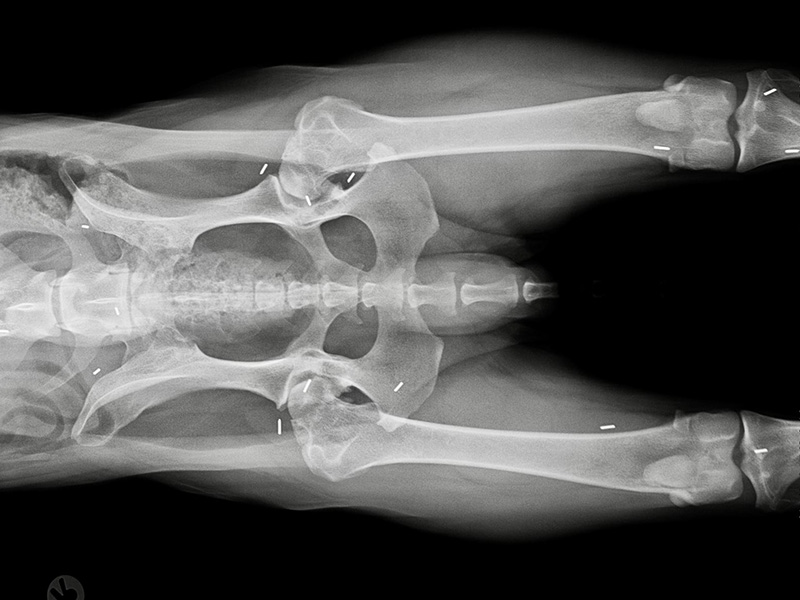

Bei der Goldakupunktur werden die Golddrahtstückchen an ganz bestimmte Akupunkturpunkte durch eine Hohlnadel unter die Haut, in die Muskulatur und / oder an Knochen verbracht. Bei genauer Kenntnis der anatomischen Grundlage dieser Punkte sowie deren Auffindung mittels feinen Ertastens können – bei entsprechendem Wissen um die Wirkung einzelner Punkte – körperliche Störungen wirkungsvoll behandelt werden.

Übrigens: Die Implantate wandern nicht und stellen auch kein Hindernis für spätere Behandlungen jeglicher Art dar.